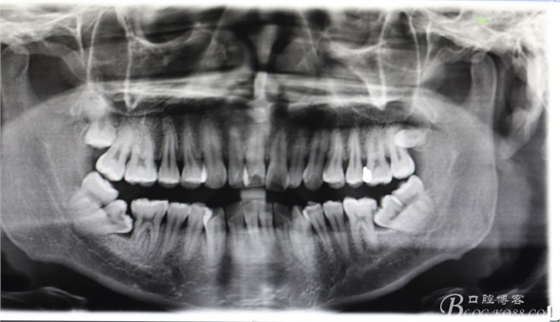

圖3.術(shù)前的全景片影像檢查:47、48疊羅漢,37、38疊羅漢。